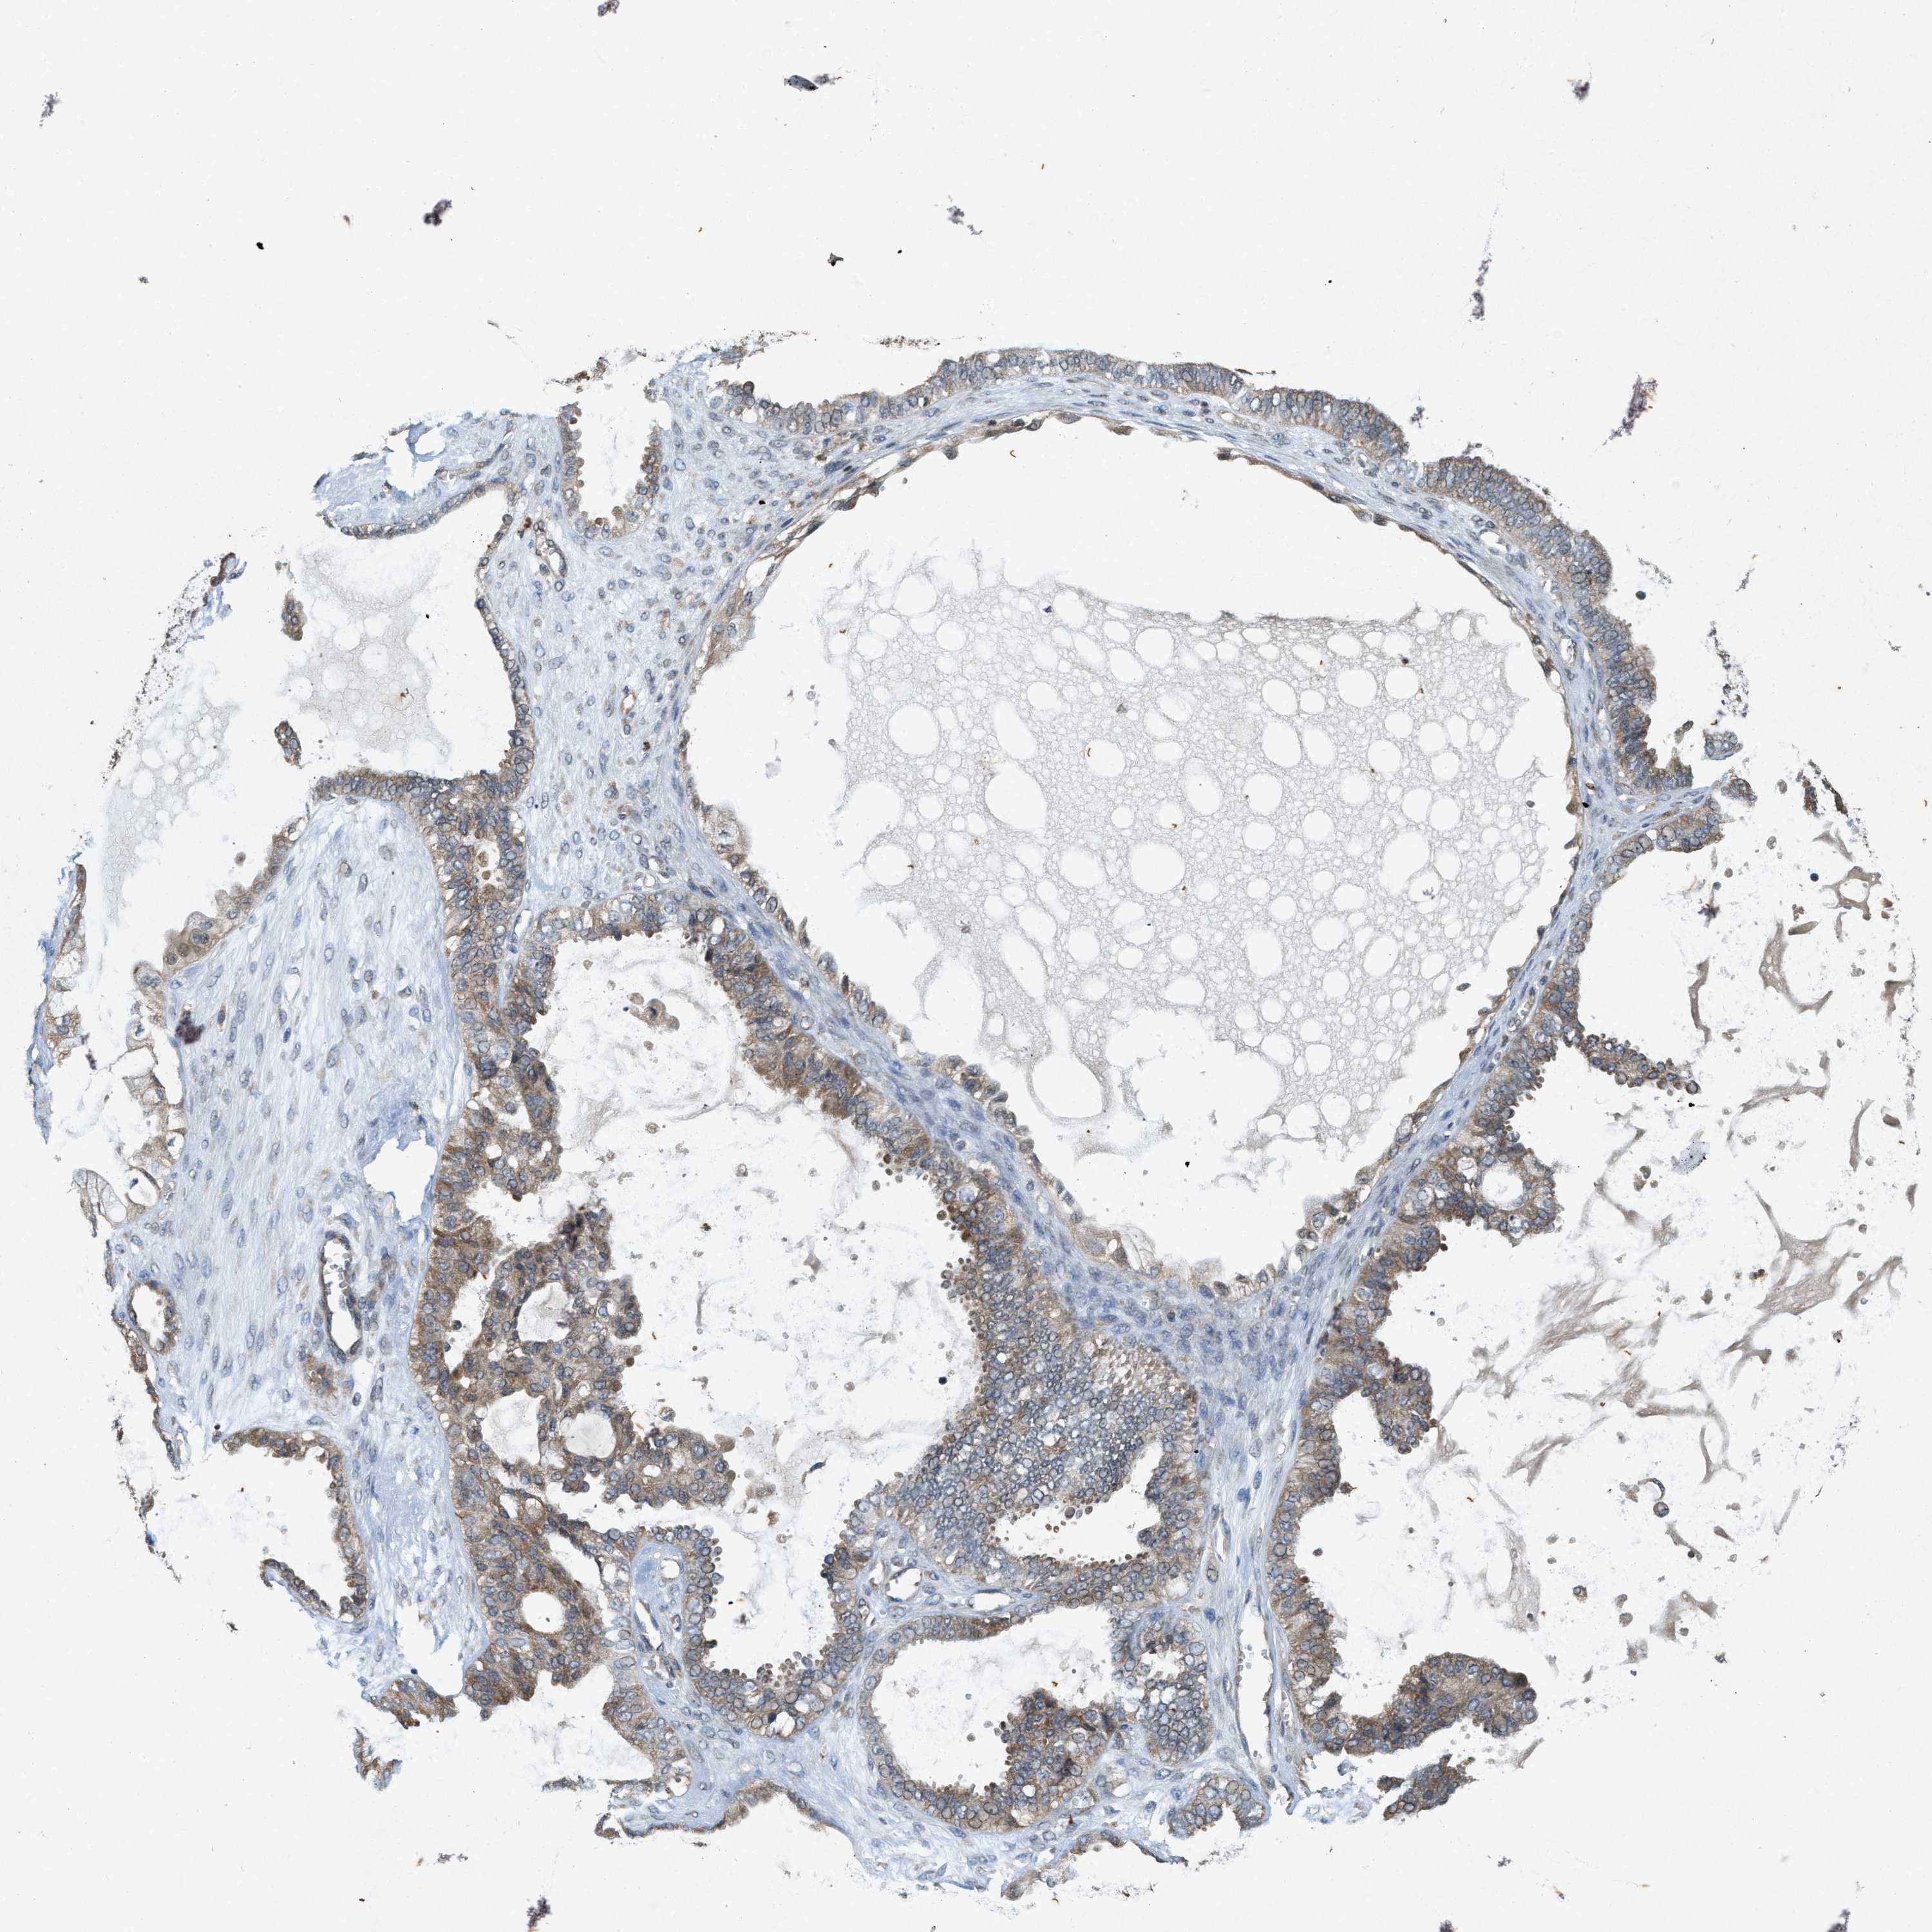

OVARIAN CANCER - Protein expressioni

A mouse-over function shows sample information and annotation data. Click on an image to view it in a full screen mode. Samples can be filtered based on level of antibody staining by selecting one or several of the following categories: high, medium, low and not detected. The assay and annotation is described here.

Note that samples used for immunohistochemistry by the Human Protein Atlas do not correspond to samples in the TCGA dataset.

Antibody stainingi

Antibody staining in the annotated cell types in the current human tissue is reported as not detected, low, medium, or high, based on conventional immunohistochemistry profiling in selected tissues. This score is based on the combination of the staining intensity and fraction of stained cells.

Each image is clickable and will lead to virtual microscopy that enables deeper exploration of all samples and also displays staining intensity scores, fraction scores and subcellular localization as well as patient and tissue information for each sample.

Antibody HPA058432

Antibody CAB022079

Cystadenocarcinoma, serous, NOS

Cystadenocarcinoma, mucinous, NOS

Adenocarcinoma, NOS

Carcinoma, endometroid

Carcinoma, NOS